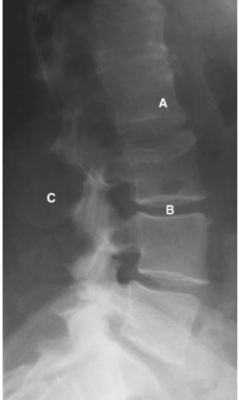

Cột sống thắt lưng

Các chữ viết tắt:

- A = L2 vertebral body; thân đốt sống L2

- B = L3/4 disc space; khoảng đĩa đệm L3/4

- C = Spinous process; mỏm gai

- D = Transverse process; mỏm ngang

- DG = Dorsal root ganglion of L2 in intervertebral foramen

- E = Sacroiliac (S–I) joint; Khớp cùng -chậu

- ES = Erector spinae muscle; cơ dựng gai

- F = Articular facet; Diện khớp nhỏ

- ID = Intervertebral disc; đĩa đệm

- L = Lamina of vertebral arch; bản cung

- L5 = L5 vertebral body; thân đốt L5

- N = Nerve root; Rễ thần kinh

- PI = Pars interarticularis; Phần liên mỏm khớp (eo)

- PL = Pedicle; cuống cung

- S = Spinal canal, cauda equina (C); ống tuỷ, đuôi ngựa

- SI = Sacroiliac joint; Khớp cùng chậu

- V =Vertebral body; Thân đốt sống